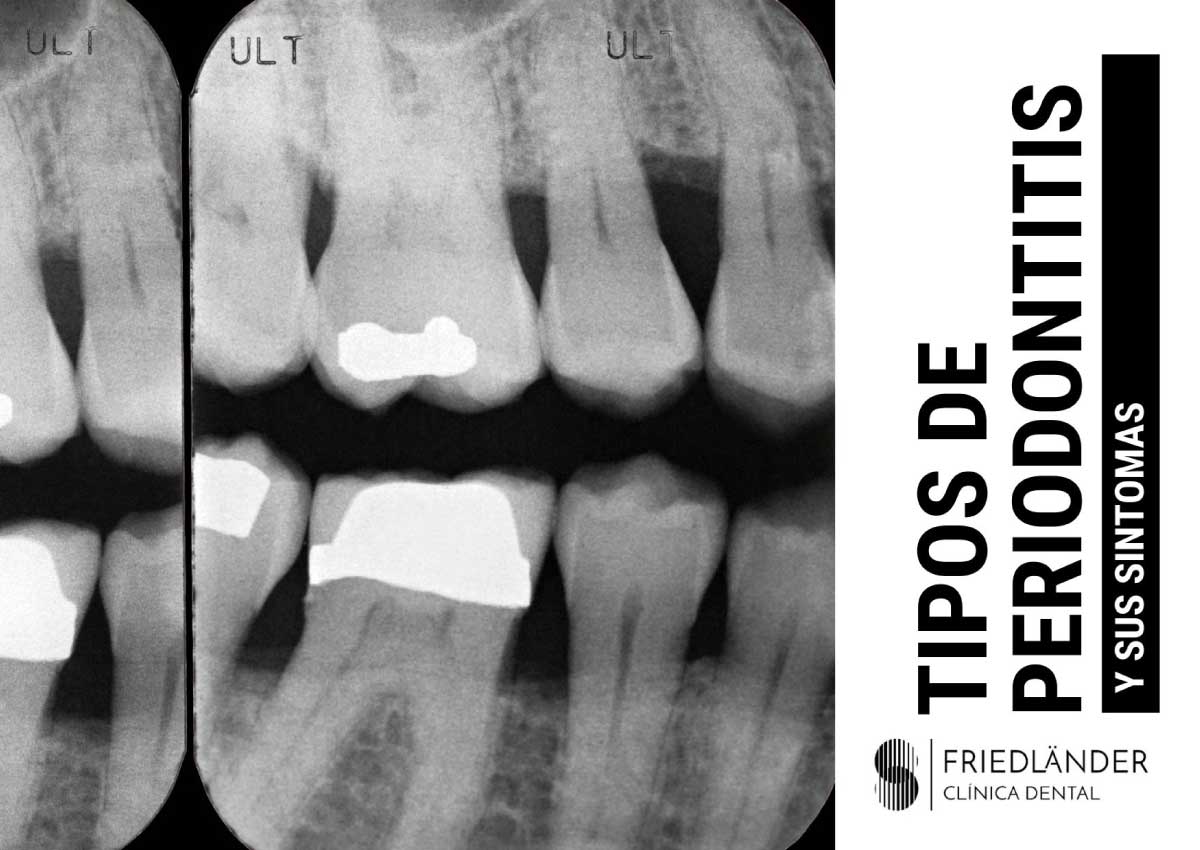

¿Cuáles son los tipos de periodontitis y cuáles son los síntomas?

Tipos de periodontitis o enfermedad periodontal

Dicho esto, los tipos de periodontitis principales son la periodontitis crónica, la periodontitis agresiva y la enfermedad periodontal necrosante.

- Pérdida rápida de soporte óseo. Este síntoma normalmente se detecta a través de radiografías dentales.